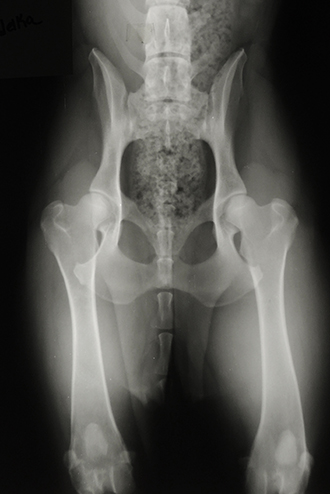

Hadelka von Schraderhaus Hips OFA Good /ED Normal DDR/East German /West Working Pedigree